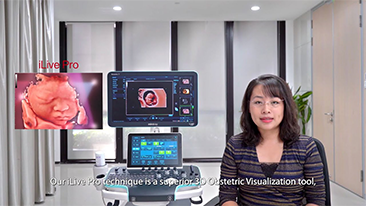

Technologia